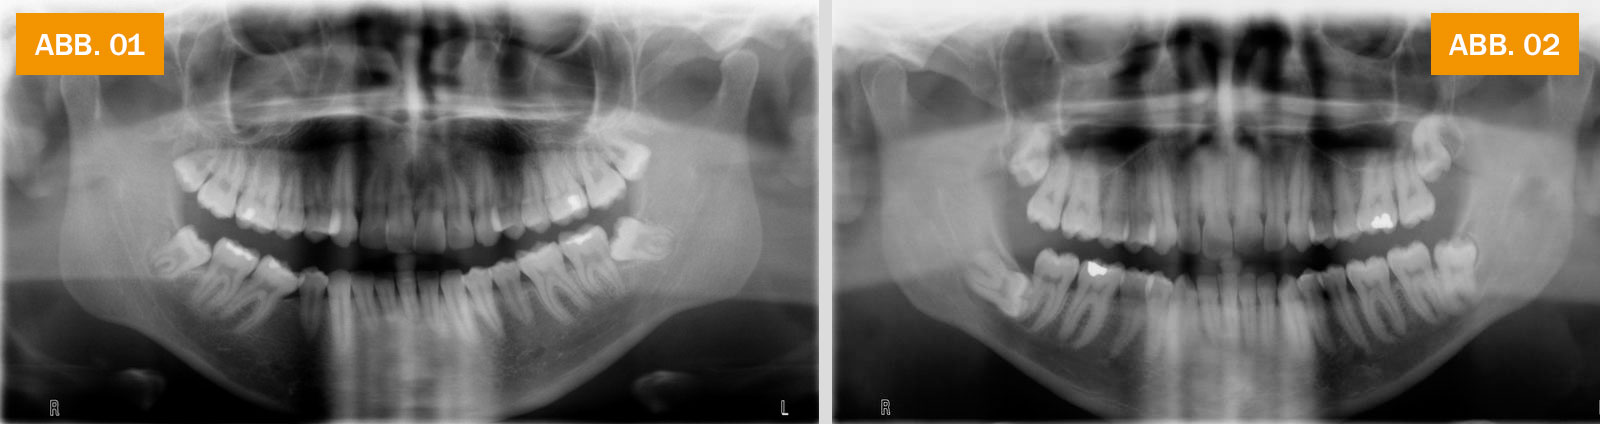

ABB. 01: Röntgenbild mit „Teilretinierten Weisheitszähnen“: Die dritten Backenzähne im Unterkiefer sind auf beiden Seiten nicht vollständig durchgebrochen und liegen schräg.